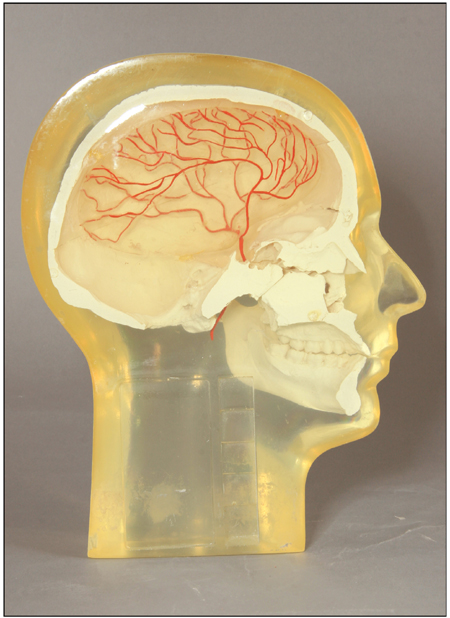

The Anthropomorphic Quality Assurance Phantom

Alderson ANGIOGRAPHIC HEAD PHANTOMS bridge the gap between physical and anatomical information requirements. Molded in tissue-equivalent material, an accurate male skull contains a 3-dimensional, high-contrast vascular simulation to facilitate correlation of the radiologist's subjective evaluation of angiographic image quality with actual measurements of resolution and contrast under the same exposure conditions.

Each ANGIOGRAPHIC HEAD PHANTOM contains a 5-step wedge. A 2-10 line pair/mm test pattern is optional. Other patterns or test objects and custom pathologies are available on special order.

The ANGIOGRAPHIC HEAD PHANTOM provides a "dry run" to completely check out angiographic equipment and ensure that it is operating satisfactorily in all significant details before subjecting patients to radiological procedures. If the imaging system malfunctions, the phantom also plays a critically important role in isolating and verifying correction of the problems. The ANGIOGRAPHIC HEAD PHANTON confines the variables to components and technique and is an invaluable service and teaching tool

Item Specs

- 3-Dimensional high-contrast vascular pattern

- Full or half-head

- Tissue equivalent materials

- Stepwedge and resolution test patterns

- Opaque or transparent